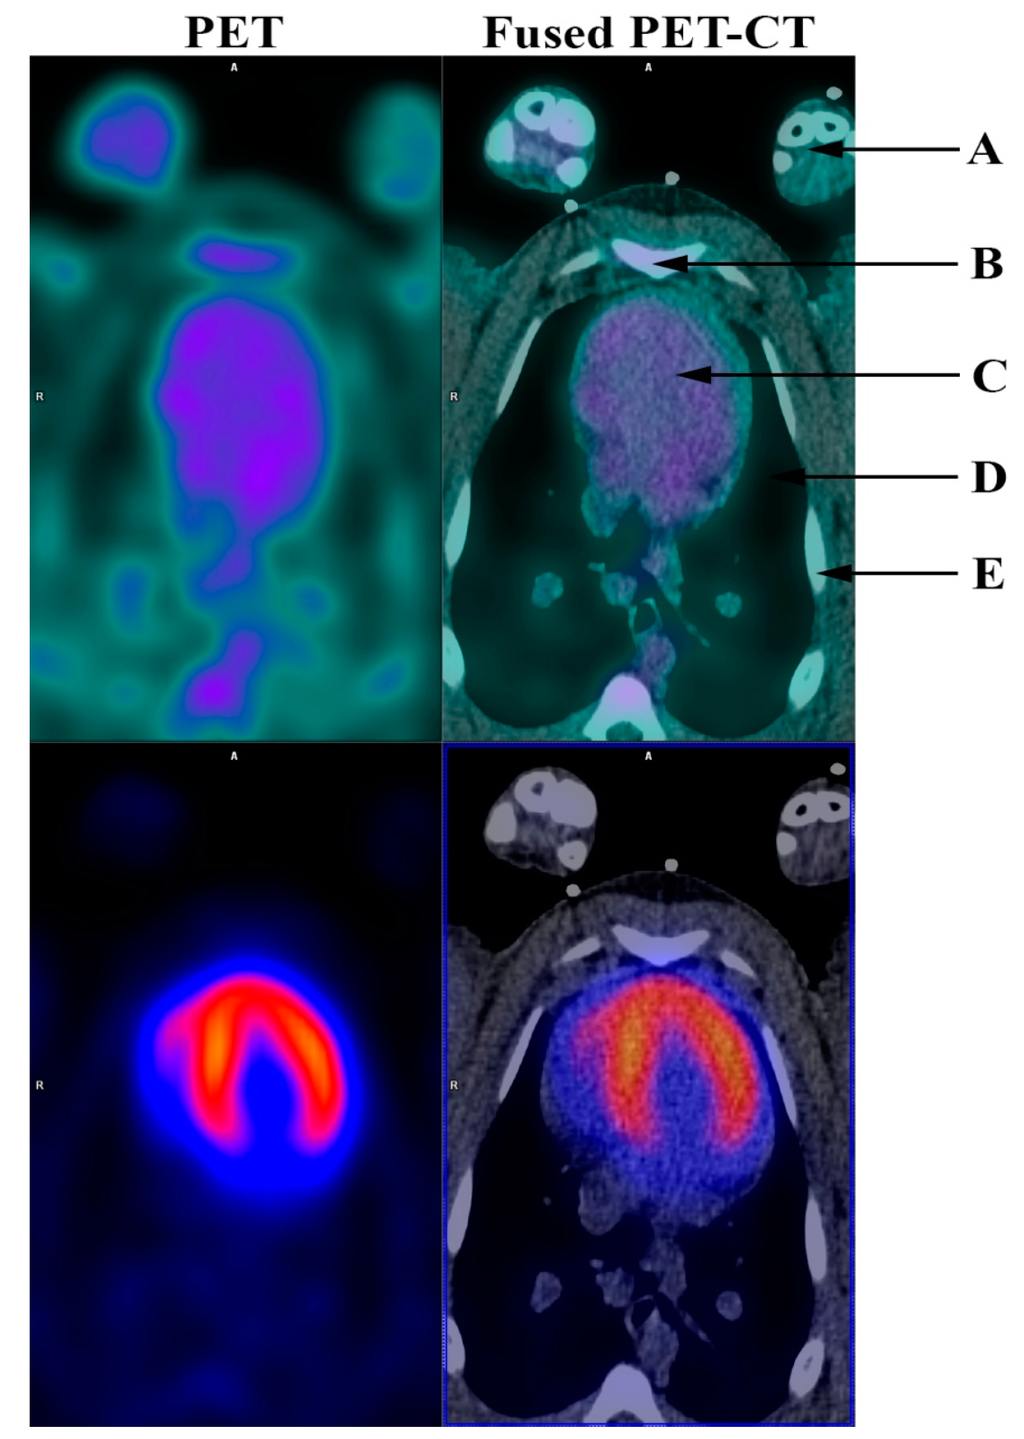

Figure 1.

Angiogenesis PET (RGD PET) (top row) and 82Rb dipyridamole stress PET (bottom row) before induced myocardial infarction. (A) Front limbs; (B) Sternum; (C) Heart; (D) Lungs; (E) Ribs. Angiogenesis is part of the healing process following an ischemic injury and is vital for the post-ischemic repair of the myocardium. It is associated with the remodeling of the left ventricle and thus prognosis following myocardial infarction [1]. Therefore, it is of particular interest to be able to noninvasively monitor angiogenesis. This might not only permit risk stratification of patients following myocardial infarction, but could also facilitate development and improvement of new therapies directed towards stimulation of the angiogenic response. During angiogenesis endothelial cells must adhere to one another to form new microvessels. This is a process modulated by the extracellular matrix including integrins. Specifically, αvβ3 integrin is highly expressed in activated endothelial cells and has been identified as a critical modulator of angiogenesis and is therefore a potential target for directly imaging angiogenesis [2,3]. Existing noninvasive imaging methods directed towards the evaluation of angiogenesis have however been somewhat limited, possibly due to the fact that myocardial angiogenesis following myocardial infarction might be focal and therefore difficult to detect. Furthermore, most of the previous studies in angiogenesis imaging have been performed in smaller animals, mostly rats [4,5,6,7,8,9,10,11,12,13]. 68Ga-NODAGA-E[c(RGDyK)]2 (RGD) has recently been developed by us as an angiogenesis positron-emission-tomography (PET) ligand targeted towards αvβ3 integrin [14]. In the present study, we induced myocardial infarction in Göttingen minipigs [15]. Successful infarction was documented by 82Rubidium (82Rb)-dipyridamole stress PET and computed tomography (CT) (Siemens mCT, Siemens, 128-slice CT, Knoxville, USA). RGD uptake was demonstrated in the infarcted myocardium one week and one month after induction of infarction by RGD-PET. The study was approved by the National Authority in Denmark (approval number: 2014-15-0201-00191). During the PET acquisition minipigs were anesthetized as described in detail previously [15]. Baseline 82Rb rest and stress myocardial perfusion were performed the week prior to induction of myocardial infarction as a 7 min dynamic PET myocardial perfusion rest scan under administration of 1000–1200 MBq 82Rb followed by a 7 min dynamic dipyridamole stress PET-CT. Dipyridamole (140 µg/kg/min) was given as a continuous intravenous infusion over 4 min prior to 82Rb-tracer injection 3–5 min after the completion of dipyridamole infusion. The RGD-PET was performed as a 10 min ECG-gated scan 45 min after administration of 100 MBq RGD. PET images were analyzed using Cedars-Sinai Cardiac Suite (Cedars-Sinai Medical Center, Los Angeles, CA, USA) for Syngo. Via (Siemens, Knoxville, TN, USA). The figure shows RGD and 82Rb stress PET images before induction of myocardial infarction. 82Rb stress PET showed even distribution of 82Rb in the left ventricle while the RGD PET showed no RGD uptake.